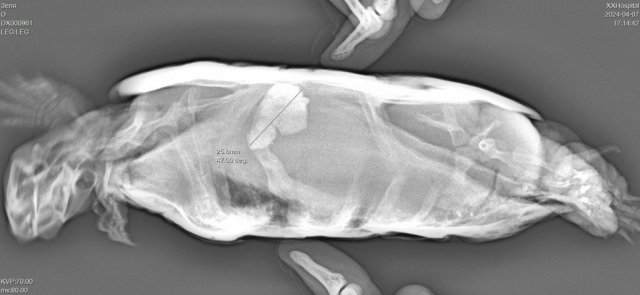

Консультанты moth Ваше имя: Мария Локация: Москва Опубликовано: 7 апреля 2024 Консультанты Опубликовано: 7 апреля 2024 @Наталья Михайлов то, что рентген сделали - хорошо то, что инородные предметы и врач Савинский - плохо, по нему много плохих отзывов было по рептилиям пару лет назад, не знаю как сейчас у него квалификация изменилась. Надеюсь в лучшую сторону. Но дело очень скверно. Такие инородные предметы это прямое показание к операции. Будет чудо, если они выйдут сами ничего не поцарапав и не порвав по пути с вазелиновым маслом. Я всё-таки советую проконсультироваться с кем-то из проверенных герпетологов, от себя бы посоветовала Николаева Ярослава, т.к. он много работал в проблемными черепахами и у него большой опыт в операциях, он хотя бы скажет всё как есть - есть тут шансы или нет https://vk.com/gyrza1937